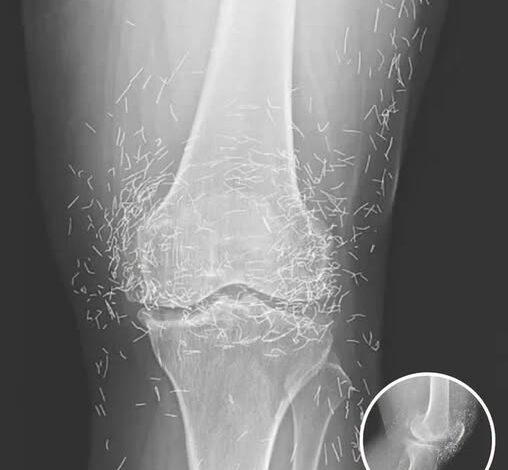

When a 65-year-old woman walked into a medical clinic in South Korea complaining of chronic, debilitating joint pain, the physicians expected to see the usual hallmarks of long-term degenerative disease. They anticipated narrowed joint spaces, telltale bone spurs, and cartilage erosion—the classic signatures of osteoarthritis. Yet, when the X-ray was developed, the team was confronted with a scene that defied conventional expectations. Staring back at them were hundreds of tiny, hair-thin gold needles, meticulously embedded deep in the tissue and muscle around her knees. This was no accident or sudden injury—it was the record of years of extreme measures taken to control pain, a physical manifestation of a decades-long struggle with osteoarthritis.

Desperate for a solution without chemical trade-offs, she turned to her culture’s deep-rooted traditions. In South Korea, acupuncture is a mainstream medical practice, widely trusted and accepted. However, the procedure she underwent went far beyond the typical insertion of needles. In a method known as gold thread or needle implantation, practitioners intentionally leave the needles inside the body. The theory is that gold provides ongoing stimulation to the acupuncture points, potentially offering a long-term reduction in pain signals. To the patient, it promised a life without pills; to the doctors examining the X-rays decades later, it raised alarms about long-term risks.

Published in the New England Journal of Medicine, her case has become a landmark warning. While she may have initially felt relief from the constant stimulation, she ultimately ended up with knees that were a literal minefield of metal. The X-rays act as a stark reminder that human bodies are not designed to house permanent foreign objects, no matter how precious the metal.